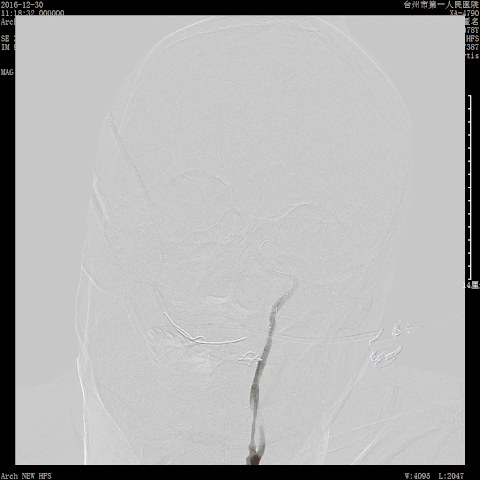

撤回颈总动脉造影,示远端情况尚可,回头造影情况良好。

![]()

术后7天NIHSS至出院时:NIHSS 2分;3个月后行走自如,mRS评分0分。